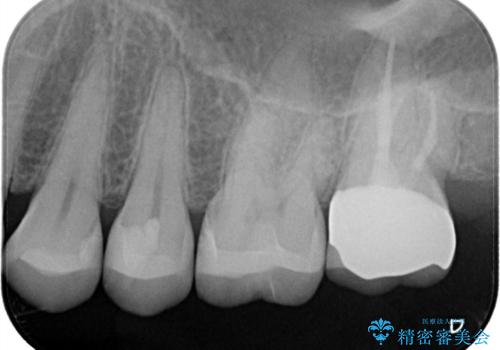

【セラミックインレー】虫歯の治療

- 定期検診にて虫歯を認めたため、セラミックインレーにて治療を行いました。

治療時にはラバーダムを装着しております。